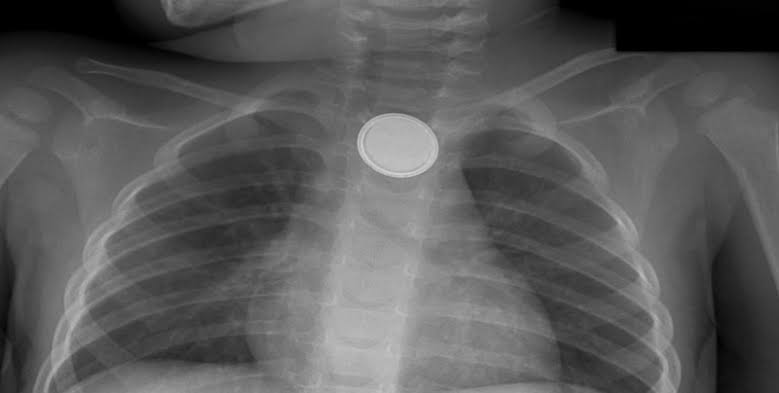

El esófago es el órgano más afectado por estos accidentes, cuando la pila permanece por mucho tiempo dentro se abre y puede liberar material tóxico que quema la mucosa, o bien liberar corriente eléctrica perforando la pared esofágica.

Las pilas de botón que se utilizan en relojes, lámparas, controles remotos, entre otros, son pequeñas y pueden ser ingeridas por los niños por curiosidad; en el caso de las pilas más grandes como la triple A y doble A, pueden ser mordidas, el líquido entra al interior en contacto con el infante, causando reacciones como vómito.